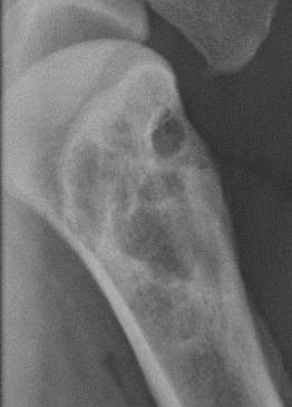

Geographic bone lysis

Moth-eaten bone lysis

Permeative bone lysis

Geographic bone lysis (multiple myeloma identified by the “punch” wound in the bone)

Moth eaten lysis

Permeative lysis

Permeative lysis and a fracture